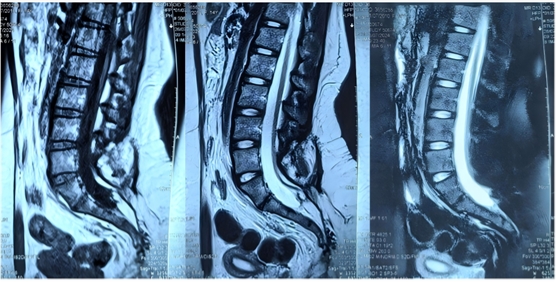

患者,女,15歲,出生后即發(fā)現(xiàn)腰骶部偏左側(cè)包塊,兩側(cè)臀部不對(duì)稱,11個(gè)月時(shí)發(fā)現(xiàn)包塊增大,考慮為脊髓拴系、脊髓脂肪瘤。2歲左右出現(xiàn)排尿費(fèi)力、尿失禁(伴尿床),遂于某兒童醫(yī)院接受脊髓拴系松解術(shù)。術(shù)后二便功能障礙進(jìn)行性加重,且出現(xiàn)下肢畸形,1年前復(fù)查發(fā)現(xiàn)脊髓拴系術(shù)后復(fù)發(fā)(圖一),遂于我科行二次松解手術(shù)。術(shù)后病情穩(wěn)定(圖二),未再有加重趨勢(shì),仍遺留大小便失禁,表現(xiàn)為小便漏尿,伴有排尿費(fèi)力,且小便都是滴出,自己不能感知。大便干燥便秘,至少三四天一次大便,大便費(fèi)力,稀的時(shí)候失禁。

圖1為1年前脊髓拴系松解術(shù)前磁共振檢查片子